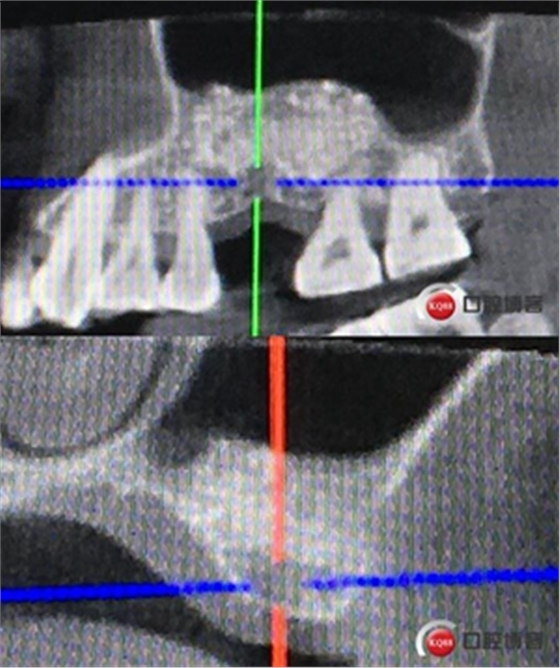

患者女性,58歲,身體健康,無不良咀嚼習慣,不吸煙、不飲酒。兩年前因左上后牙反復咬合痛,嚴重影響進食就診,檢查發(fā)現26號牙根尖周炎癥明顯,周圍骨吸收嚴重。拔除患牙,徹底掻刮,由于骨缺損嚴重,沒能即刻種植。6個月后來門診種植。

骨高度僅有3mm,寬度充足。計劃外提升,根據骨質情況決定是否同期植入植體,切開翻瓣,暴露上頜竇頰側骨壁。

骨高度比曲斷片顯示的更低,不利于同期植入,直接縫合。

術后X光片,植骨量充足。

術后8個月,X光顯示骨量充足,密度明顯增加。